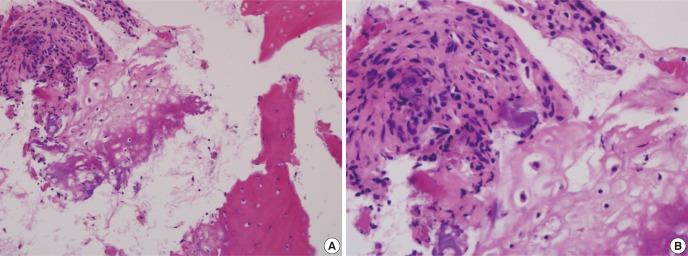

Fibrocartilaginous dysplasia (FCD) has occasionally led to a misdiagnosis and wrong decision which can significantly alter the outcome of the patients. A 9-yr-old boy presented with pain on his left distal thigh for 6 months without any trauma history. Initial radiographs showed moth eaten both osteolytic and osteosclerotic lesions and biopsy findings showed that the lesion revealed many irregular shaped and sclerotic mature and immature bony trabeculae. Initial diagnostic suggestions were varied from the conventional osteosarcoma to low grade central osteosarcoma or benign intramedullary bone forming lesion, but close observation was done. This study demonstrated a case of unusual fibrocartilaginous intramedullary bone forming tumor mimicking osteosarcoma, so that possible misdiagnosis might be made and unnecessary extensive surgical treatment could be performed. In conclusion, the role of orthopaedic oncologist as a decision maker is very important when the diagnosis is uncertain.

纤维软骨发育不良(FCD)偶尔会导致误诊和错误决策,从而显著改变患者的预后。一名 9 岁男孩因左大腿远端疼痛就诊,病史 6 个月,无外伤史。初始 X 线片显示虫蚀样溶骨性和硬化性病变,活检结果显示病变有许多不规则形状和硬化成熟及未成熟骨小梁。最初的诊断提示从常规骨肉瘤到低度中央骨肉瘤或良性髓内成骨病变不等,但进行了密切观察。本研究显示了一例不寻常的纤维软骨性髓内成骨肿瘤,类似于骨肉瘤,因此可能会出现误诊,并可能进行不必要的广泛手术治疗。总之,当诊断不确定时,矫形肿瘤学家作为决策者的作用非常重要。